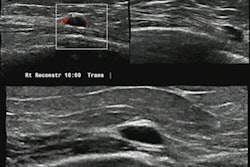

The women were divided into two sets, 330 for a training set and 147 for a validation set. The team reviewed ultrasound and mammography features. The clinical model included lesions that presented as a mass at ultrasound without microcalcification and no comedonecrosis at biopsy. This was used to identify low-nuclear-grade DCIS.

The team wrote that low-nuclear-grade DCIS lesions manifesting as a mass at ultrasound without microcalcifications at mammography and no comedonecrosis at biopsy were not upgraded at surgery.